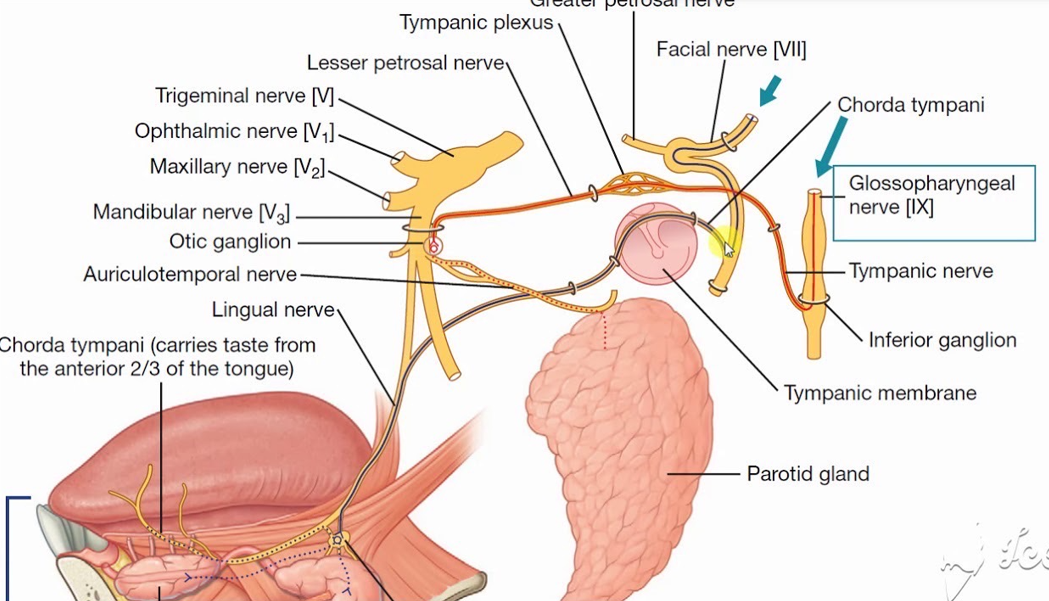

Chorda Tympanic n.(Parasymphysis)

- 支配前味覺

- Submandibular, Sublingual g.

CN IX

- Lesser petrosal n.(Parasymphysis)

- 支配Parotid g.的副交感節前神經

- Tympanic n.

- 中耳、鼓膜內面、耳咽管(Eustachian)